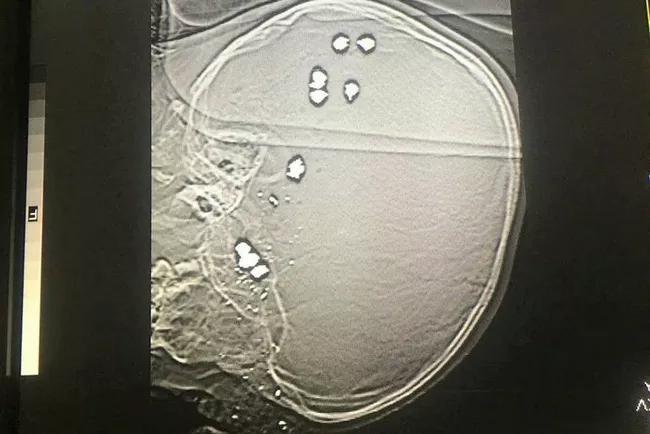

01/04/2022 15:17Nghịch súng, bé trai bị 11 viên đạn bi găm vào đầu tử vong

Sáng 1/4, ông Trương Công Thành - Phó khoa Cấp cứu, Bệnh viện Sản Nhi tỉnh Ninh Bình - xác nhận với Dân Việt, bé trai B.T.P (6 tuổi, quê huyện Lạc Thủy, tỉnh Hòa Bình) nhập viện trong tình trạng hôn mê sâu, suy hô hấp, mất nhiều máu, trong đầu có 11 viên đạn bi... Sau đó, gia đình xin đưa bé trai về nhà.

Chia sể với tờ báo trên, ông Thành thông tin chi tiết: "Khoảng 10 giờ ngày 29/3, chúng tôi nhận được cuộc điện thoại báo có cháu B.T.P (người tỉnh Hòa Bình) bị nhiều viên đạn bi găm vào đầu cần cấp cứu gấp.

Đến 11 giờ 26 phút cùng ngày, cháu P được đưa tới bệnh viện trong tình trạng hôn mê sâu, suy hô hấp, mất nhiều máu… Chúng tôi đã nhanh chóng xử trí, hồi sức tích cực, cho cháu P thở máy, thay băng vết thương, mời hội chẩn khẩn cấp.

Tiến hành xét nghiệm, chụp chiếu, chúng tôi phát hiện trong đầu cháu có 11 viên đạn bi, không còn khả năng cứu chữa... Sau đó, gia đình cháu B.T.P đã xin làm thủ tục để đưa cháu về nhà và qua nguồn tin báo lại cho biết cháu P đã tử vong sau đó, thật xót xa".

Qua điều tra ban đầu, gia đình cháu B.T.P cho biết, ở nhà cháu P nghịch súng kíp của gia đình, không may súng cướp cò và cháu bị nhiều viên đạn găm vào đầu. Gia đình nhanh chóng đưa cháu bé đến Bệnh viện huyện Yên Thủy, tỉnh Hòa Bình để sơ - cấp cứu, sau đó chuyển đến Bệnh viện Sản Nhi tỉnh Ninh Bình.